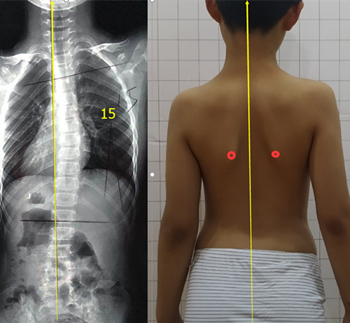

青少年脊柱側(cè)彎一旦被家長(zhǎng)發(fā)現(xiàn),應(yīng)積極治療,阻止側(cè)彎進(jìn)一步加重。但也有一些孩子,在發(fā)現(xiàn)脊柱側(cè)彎后,由于醫(yī)生判斷失誤,家長(zhǎng)不重視等等原因,沒(méi)有采取任何治療。發(fā)育期的孩子明顯增加較快,每個(gè)月基本增加1度。每年12度左右。

盡早展開(kāi)學(xué)校脊柱側(cè)彎篩查,在30度以?xún)?nèi)發(fā)現(xiàn),最后可以治療到低于20度。如果這樣,對(duì)孩子的影響幾乎可以忽略。